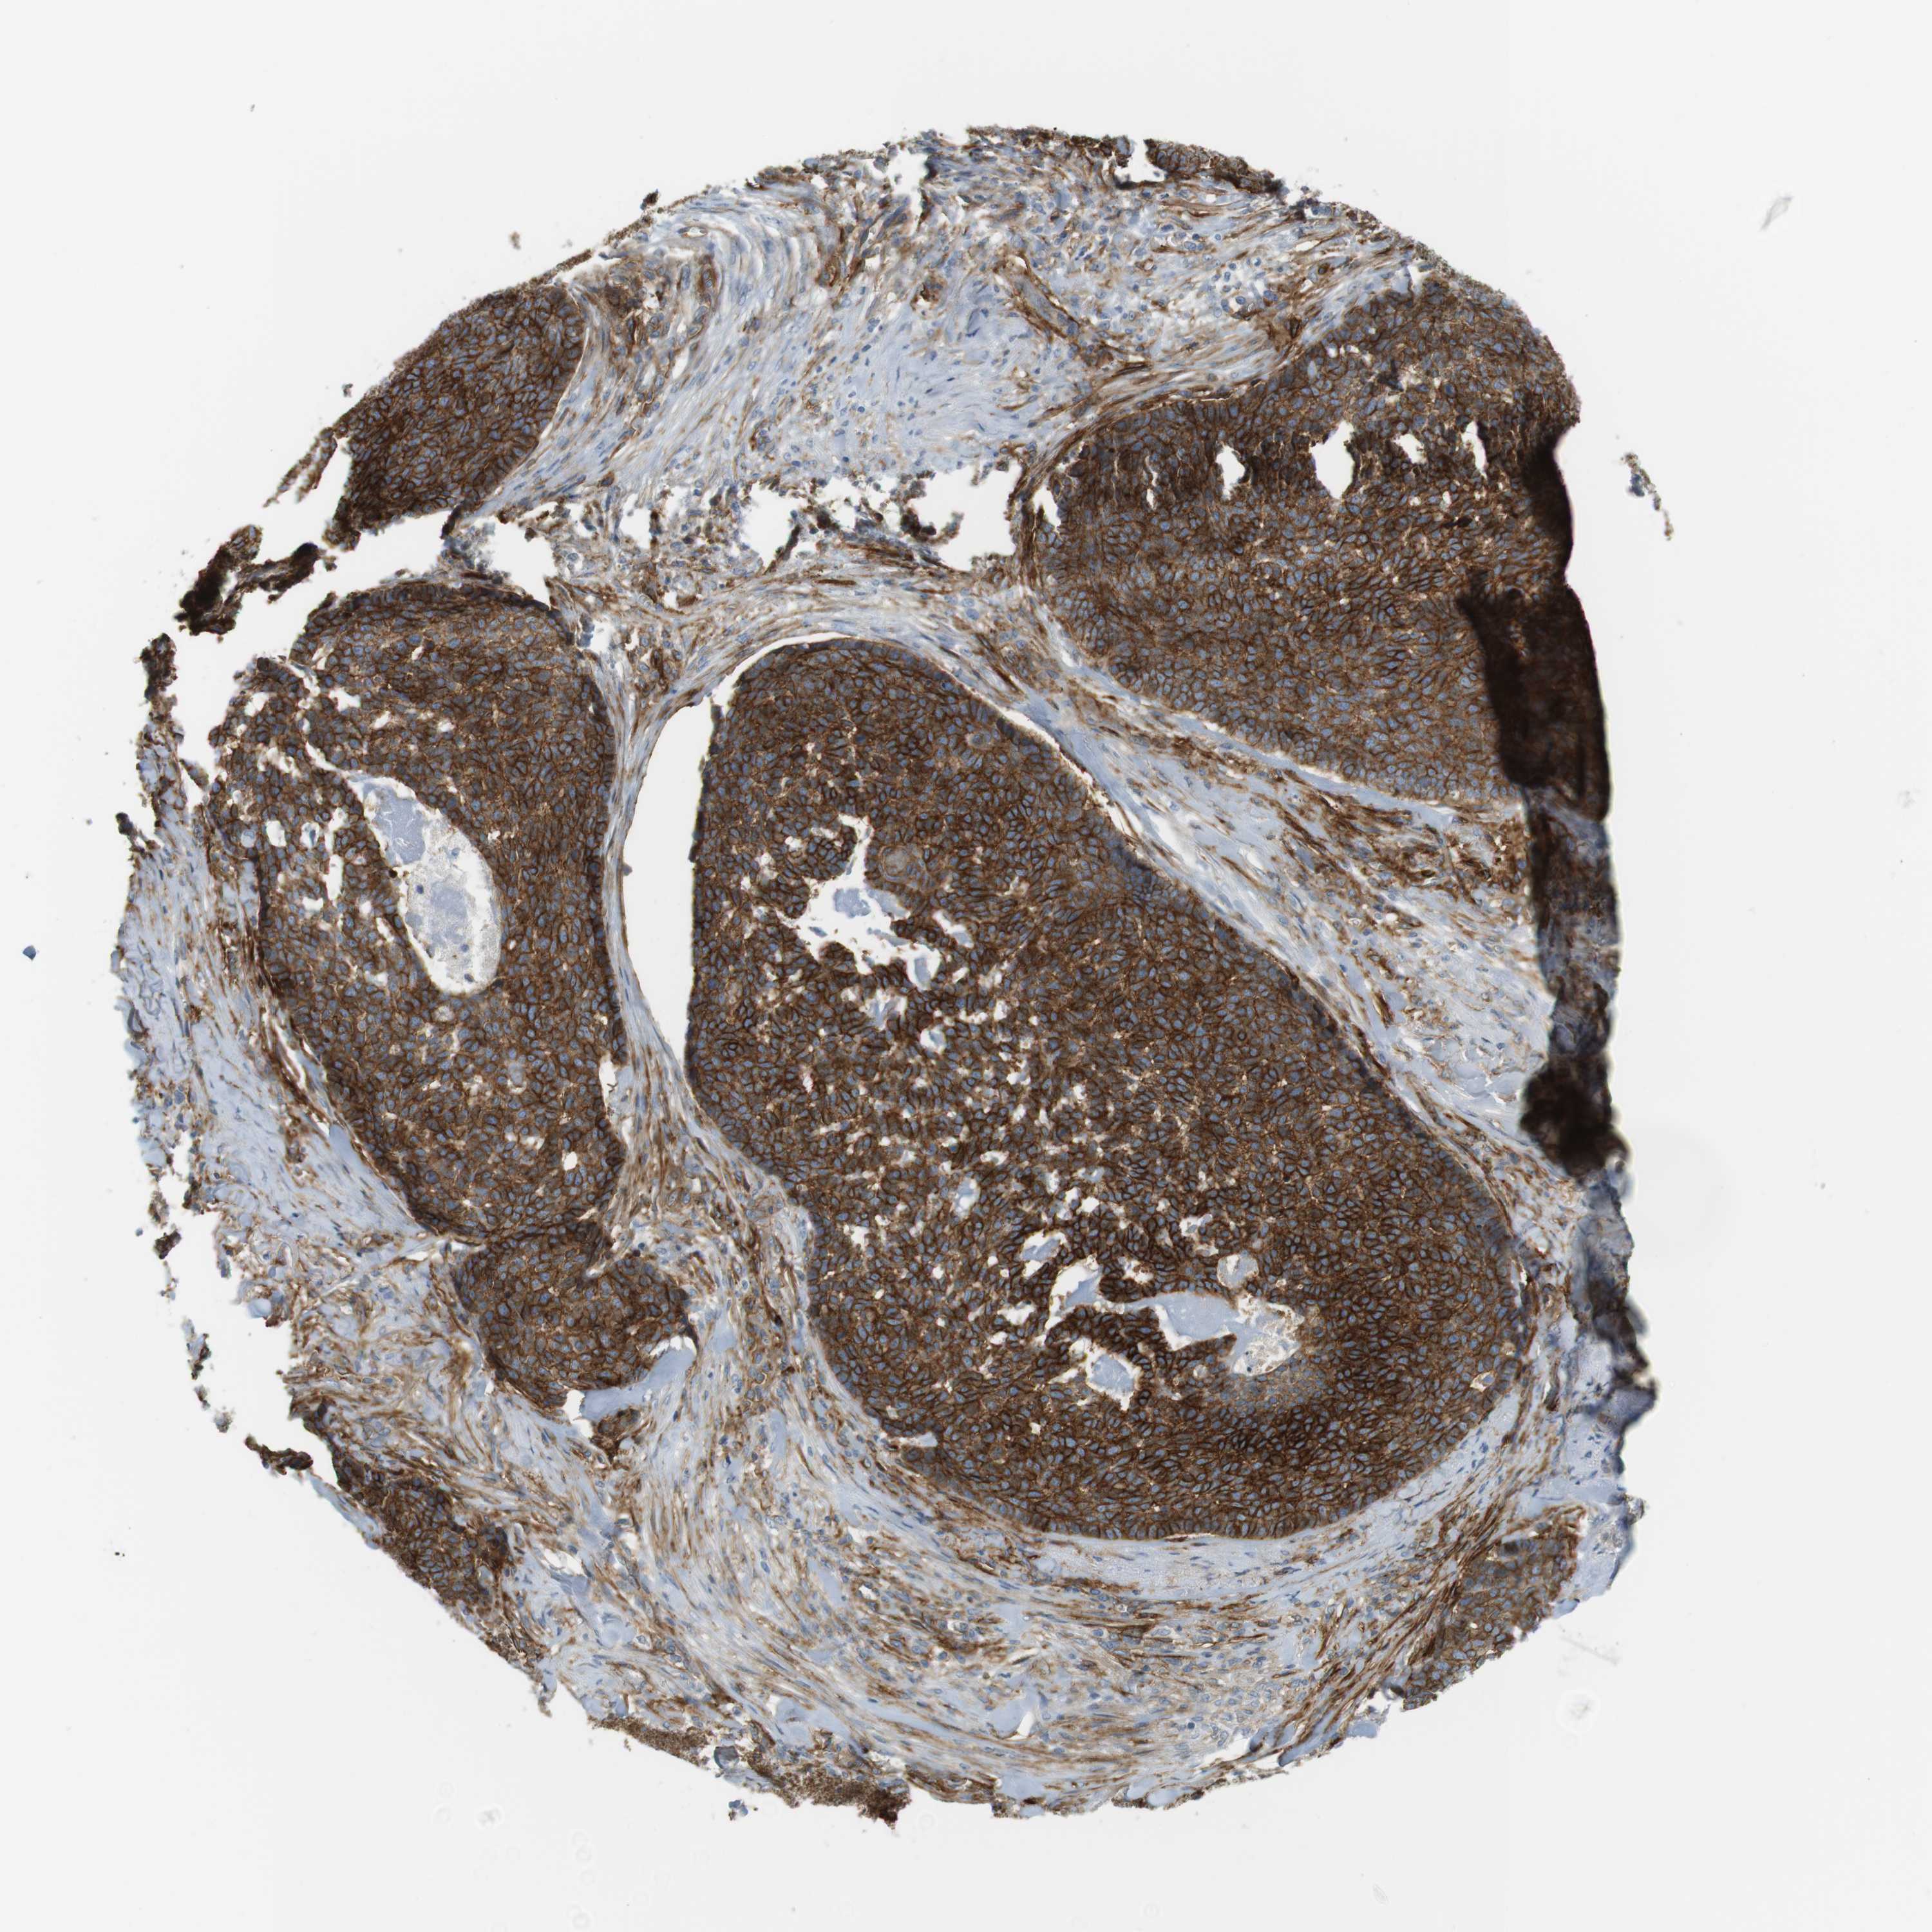

Basal cell and squamous cell cancer

SKIN CANCER - Protein expressioni

A mouse-over function shows sample information and annotation data. Click on an image to view it in a full screen mode. Samples can be filtered based on level of antibody staining by selecting one or several of the following categories: high, medium, low and not detected. The assay and annotation is described here.

Each image is clickable and will lead to virtual microscopy that enables deeper exploration of all samples and also displays staining intensity scores, fraction scores and subcellular localization as well as patient and tissue information for each sample.

Antibody CAB012962

Staining

High

Intensity

Strong

Quantity

>75%

Location

Nuclear

Squamous cell carcinoma, NOS

Basal cell carcinoma

Adnexal tumor, benign